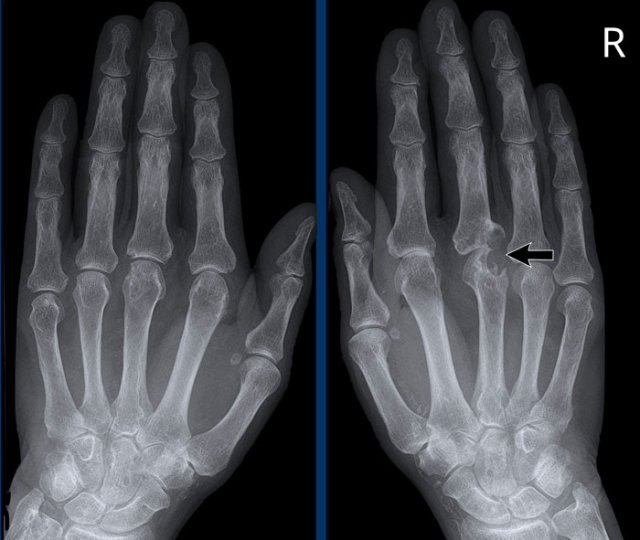

Typical marginal erosions and joint space narrowing of MCP 3-5.

Also note the uniform joint space narrowing of the MCP joints.

The PIP-joints only show minimal joint space narrowing.

End stage Rheumatoid arthritis. End stage Rheumatoid arthritis.

This is a case with end stage rheumatoid arthritis with severe erosive changes and ligamentous ruptures causing dislocation of the MCP joints.

Scapholunate dissociation (white arrow) is a common finding due to diffuse carpal inflammation. Both the dissociation and inflammation can cause joint space narrowing in the radiocarpal joint.

Notice also the erosion in the distal ulna with surrounding soft tissue swelling (blue arrow).

Rheumatoid arthritis in the feet Rheumatoid arthritis in the feet

In this case of rheumatoid arthritis there are marginal erosions adjacent to almost all MTP joints (arrowheads).

The 5th MTP joint is most frequently involved in  rheumatoid arthritis.

When erosions are as severe as in this case, it can look like pencil-in-cup deformity (white arrow) as is frequently seen in psoriatic arthritis.

However, the primarily affected MTP joints distribution and less affected interphalangeal joints is the clue that this is a case of rheumatoid arthritis.